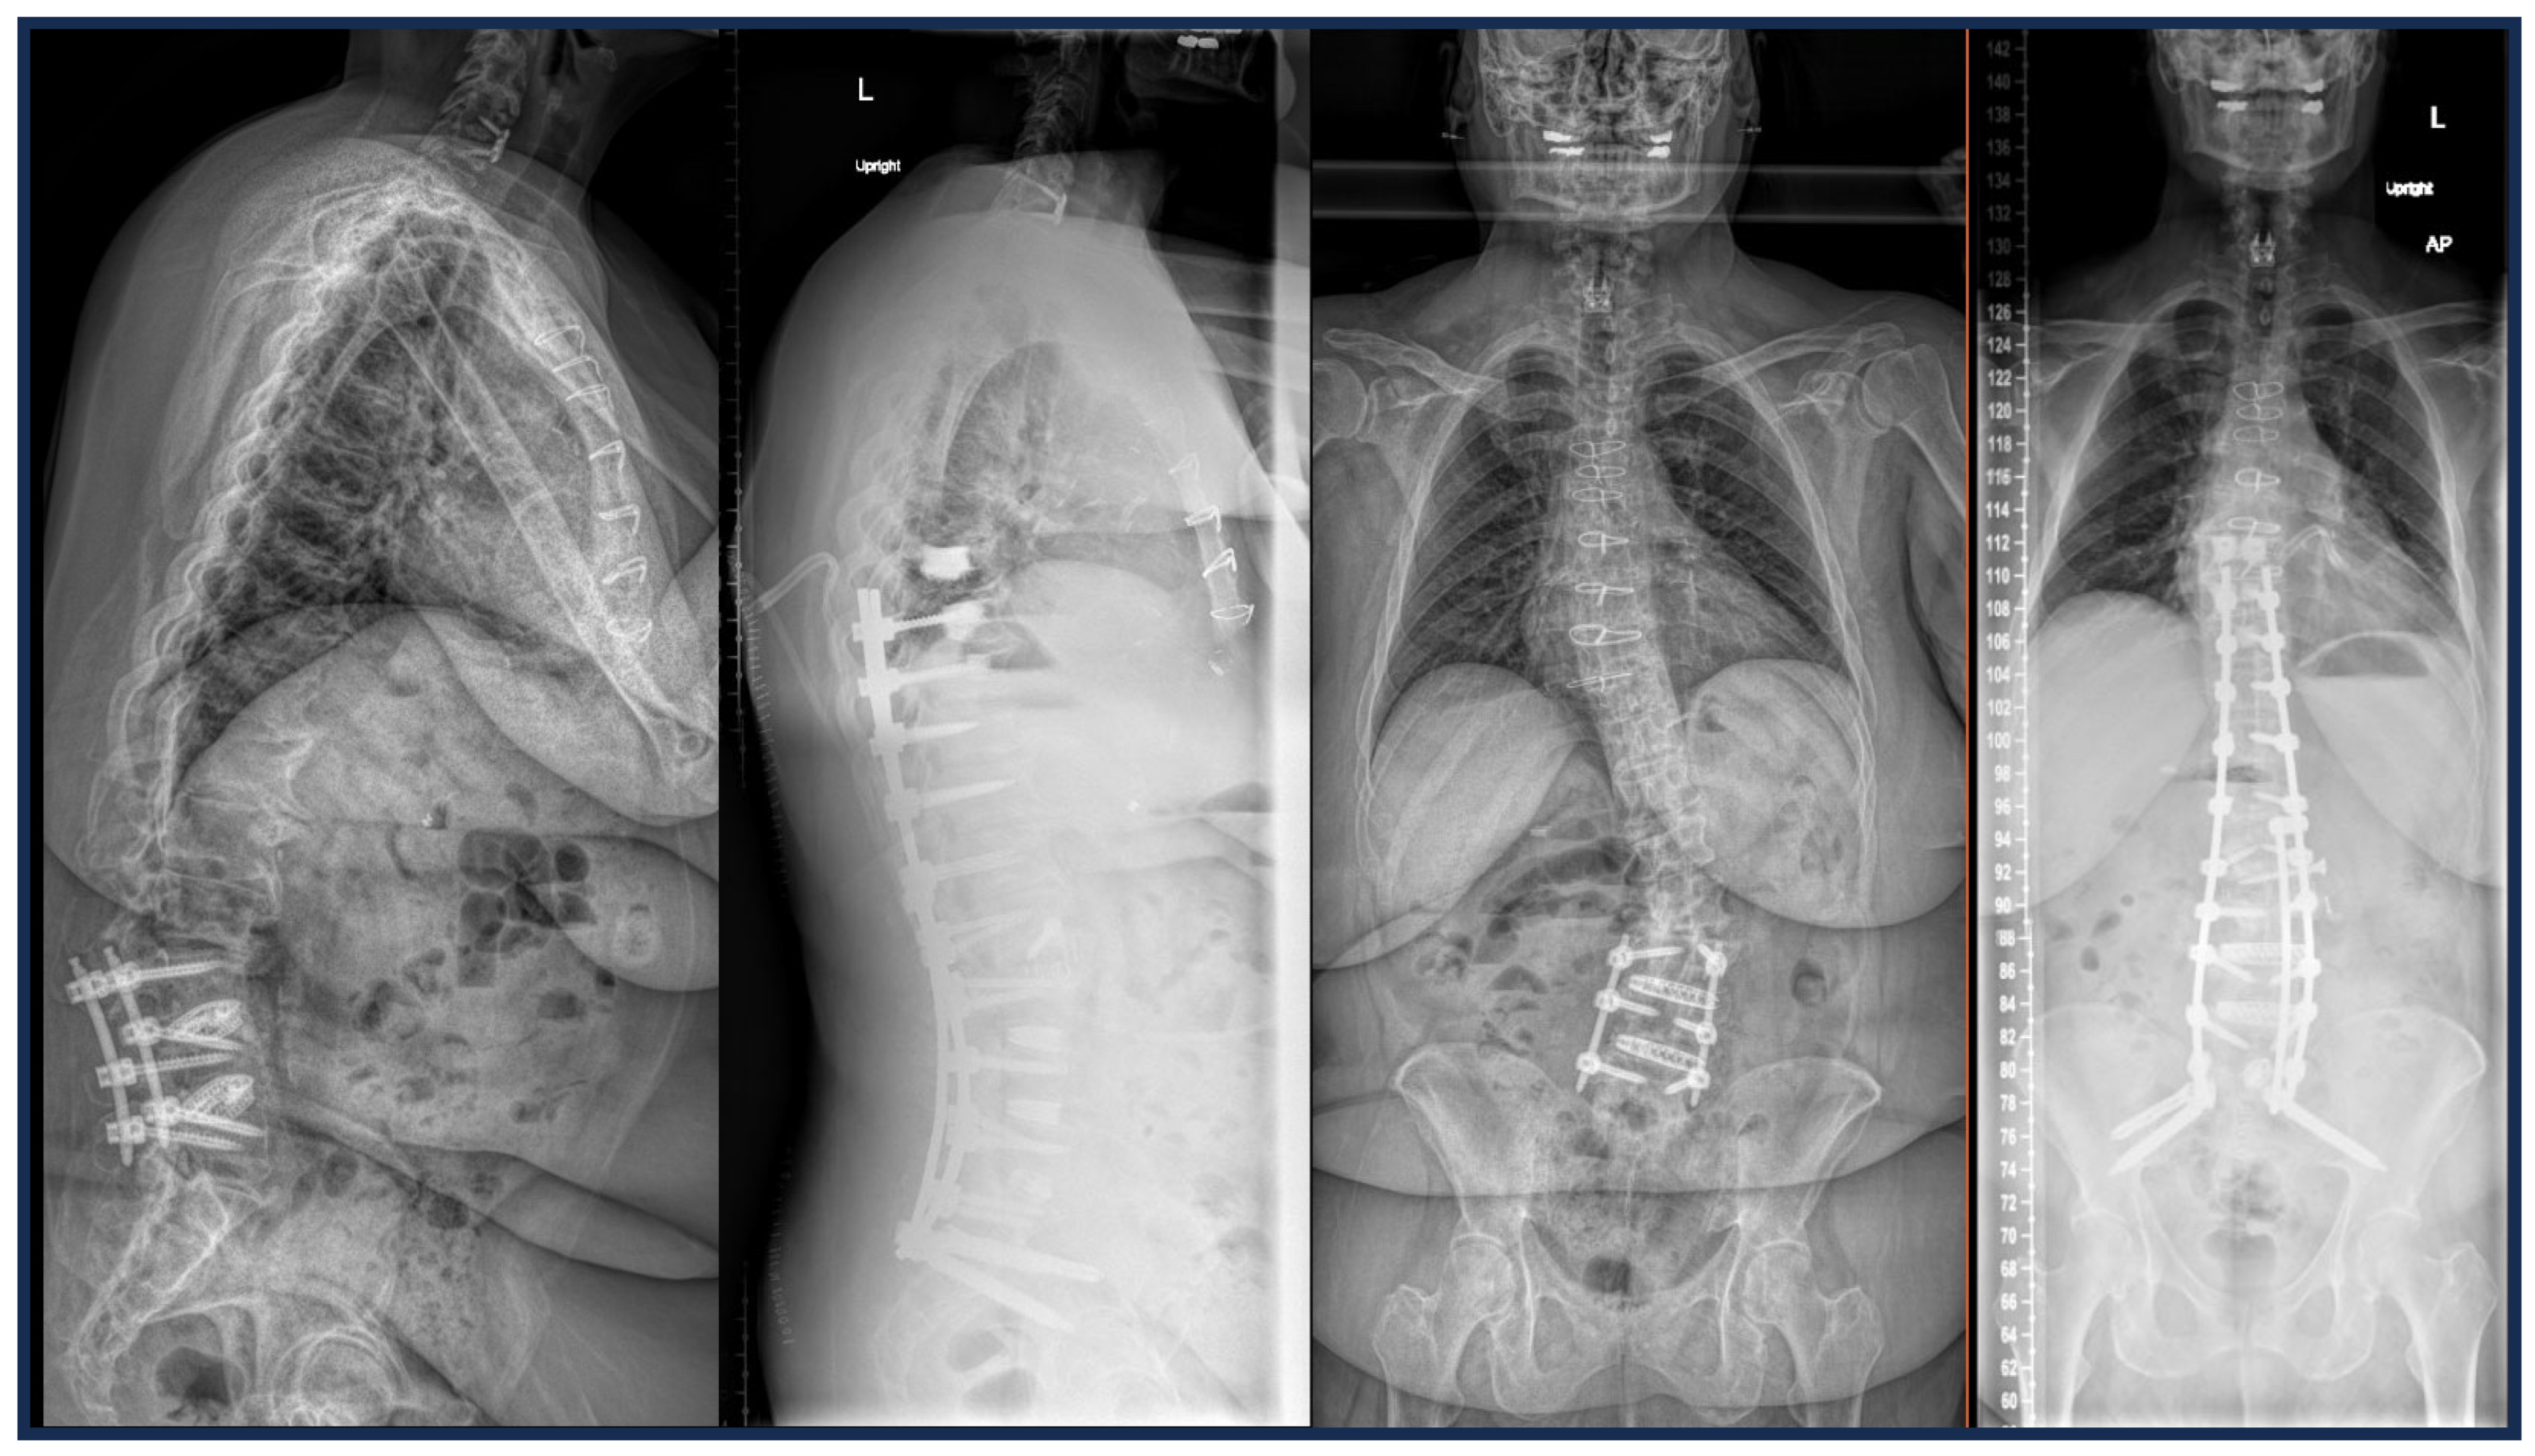

2.1. Advances in Deformity Imaging

2.4. Preoperative Planning and Predictive Modeling

2.8. PJK Prevention: Tethers, Hooks, Kyphoplasty